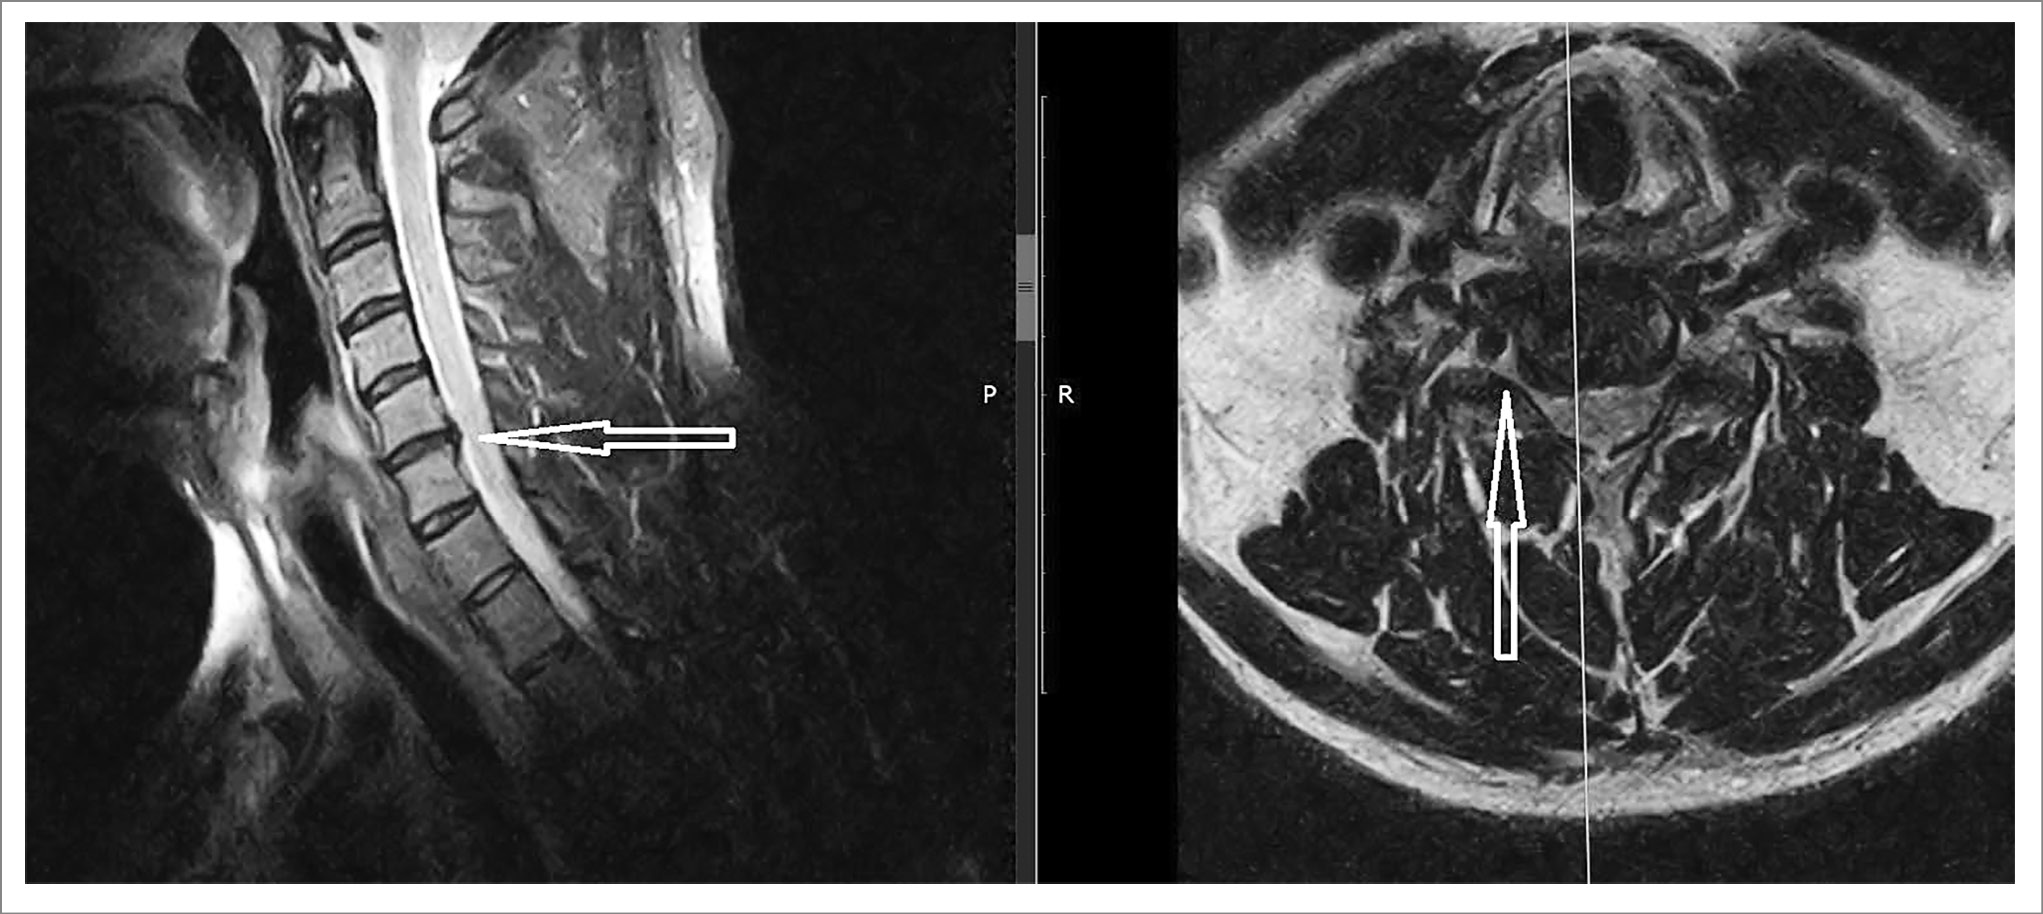

Амбулаторно проведена магнитно-резонансная томография (МРТ) ШОП. Заключение: выявлены изменения в субхондральных отделах тел позвонков (по типу Modic-2), дугоотросчатые суставы и унко-вертебральные сочленения умеренно дегенеративно изменены на уровне С5-С6, высота межпозвонковых дисков умеренно снижена на уровнях С5-С7, структура дисков изменена за счет начальных проявлений дегидратации; обнаружена правосторонняя лаерализованная (до 3,1 мм) грыжа диска С5-С6 с умеренной деформацией переднего контура дурального мешка, мелкими краевыми заострениями, корешковые отверстия сужены, больше справа, отмечено контактное воздействие на корешки нервов с признаками компрессии, позвоночный канал сужен до 8,5 мм (рис. 1).

Рис. 1. МРТ ШОП пациента И. Правосторонняя грыжа диска С5-С6 (показана стрелкой) с умеренной деформацией переднего контура дурального мешка.

Основным методом нейровизуализации для пациентов с впервые возникшей или нарастающей клинической картиной нетравматической ЦР, в отсутствие «красных флагов тревоги», является МРТ ШОП без контрастирования [19]. В представленном клиническом случае выявлены МРТ-изменения в виде преимущественно фораминального стеноза, обусловленного относительно небольшими разрастаниями в области унковертебральных сочленений, «жестким» диско-остеофитным комплексом, которые лучше видны на снимке в аксиальной проекции (см. рис. 1).